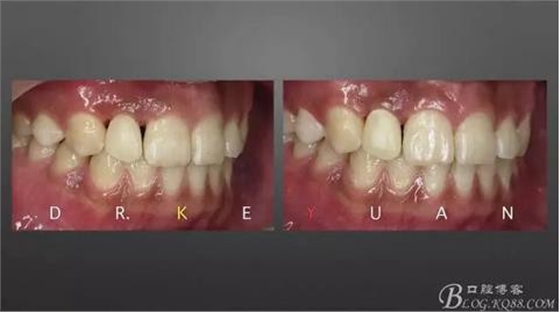

CASE 4—18歲少年,冠折后半年來診

1、術(shù)前比色

13、術(shù)前術(shù)后對比